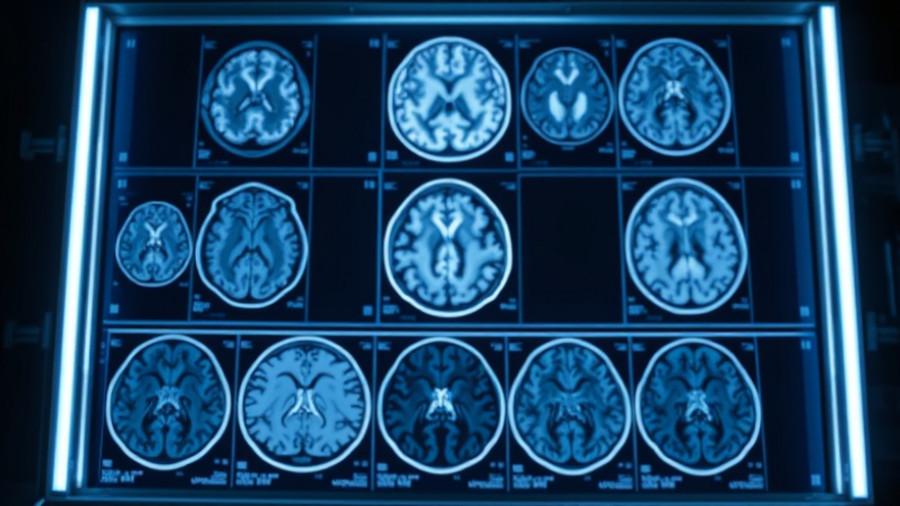

Recent studies are revealing alarming patterns regarding the cognitive health of men as they age, particularly in the context of Alzheimer’s disease. A significant takeaway from extending research is that men experience a faster rate of brain shrinkage than women. This peculiar trend raises questions about how aging affects the overall brain health and the prevalence of neurodegenerative diseases like Alzheimer’s.

According to a longitudinal study highlighted by researchers at the Proceedings of the National Academy of Sciences, men showed a greater decrease in brain volume across various regions compared to women. This shrinkage is especially prominent in areas such as the postcentral cortex—a region crucial for processing sensory information. The findings suggest a connection between accelerated brain aging in men and their cognitive health outcomes.